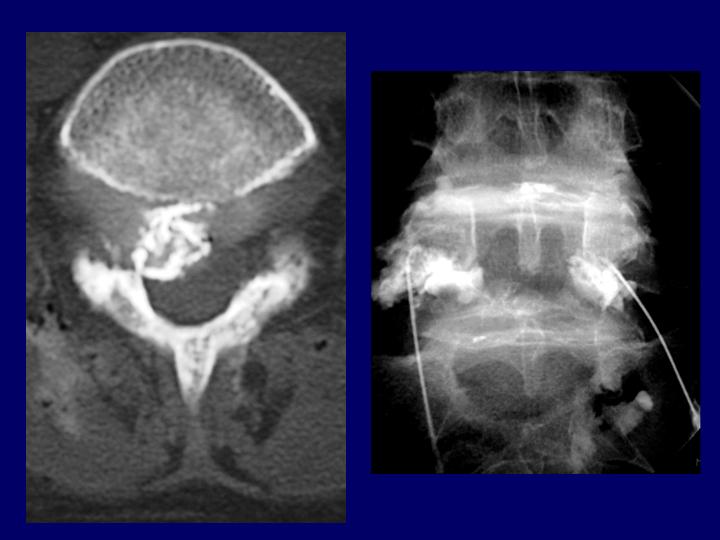

Hernias Discales